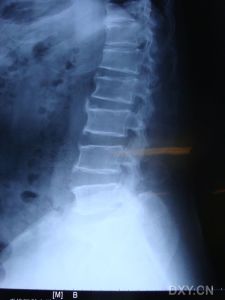

(2)酶活性測定:測定末梢血白細胞中的酶活性,是診斷和鑑別各型黏多糖增多症的主要依據。其他輔助檢查: 1.X線檢查 (1)MPSⅠ型:在MPSⅠ型的各亞型中,骨骼改變的X線表現亦是以Hurler綜合徵最為嚴重。 ①頭顱:出生後6個月以內基本正常。其後逐漸出現顱縫早閉,前囟門閉合延遲。頭顱前後徑增大呈舟狀。腦脊膜增厚可引起阻塞性腦積水,可使頭顱進一步增大。蝶鞍前後徑增大,呈仰臥的“J”形或鞋形;有蛛網膜下囊腫者,可出現蝶鞍增大。顱骨板緻密,板障增厚,顱底及眶頂亦有硬化。蝶竇、乳突與鼻旁竇發育及氣化不良。下頜骨粗短,鉤狀突發育不良,呈扁平或凹陷,踝狀窩變淺、不規則。牙齒小,排列稀疏、不齊,磨牙常位於下頜支內。 ②脊柱:椎體上下緣呈雙凸或橢圓形,齒狀突短小,可有寰樞關節半脫位。胸椎下段和腰椎上段(胸12、腰1或腰1、腰2)椎體短小,呈卵圓形,其前下緣變尖,呈“鳥嘴”樣突起,並向後移位形成後凸畸形。 ③胸廓:肋骨脊柱端細小,中段至胸骨端逐漸增寬,呈“船槳”樣改變。鎖骨內側段明顯增粗,外側段較細並上翹。肩胛骨位置升高,略呈等邊三角形,下角變尖,肩胛盂淺而小,甚至消失。肱骨頭扁小,頸-乾角變小,甚至可呈直角,可有內翻畸